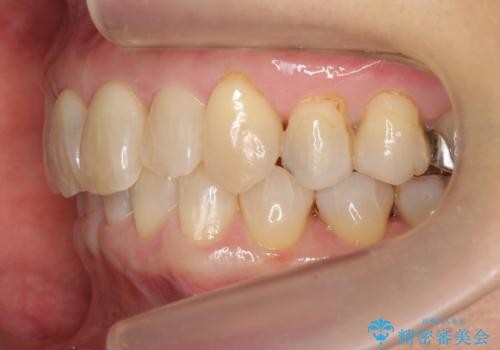

50代女性 インビザライン かみ合わせが深く、難しい症例

かみ合わせが深く、上の歯が咬みこんで下の歯にワイヤーがつけられない状態で、ワイヤー矯正はかなり難しい状態でした。

反対咬合や、すれ違い咬合もあり、大変難しいケースでしたが治療することができました。